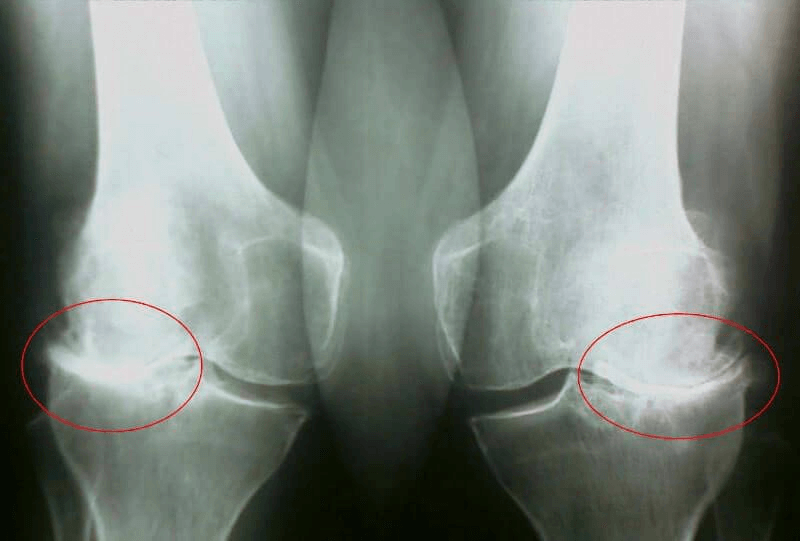

Rendgen sa očiglednim znacima artroze

- Dan 35: Otišao sam doktoru i napravio rendgenski snimak. Nema tragova artroze! Hrskavica u zglobovima kao kod 20-godišnjeg klinca.

Doktorka je rekla da je prethodni rendgen najverovatnije imao defekt, pa je dijagnoza artroze pogrešna.